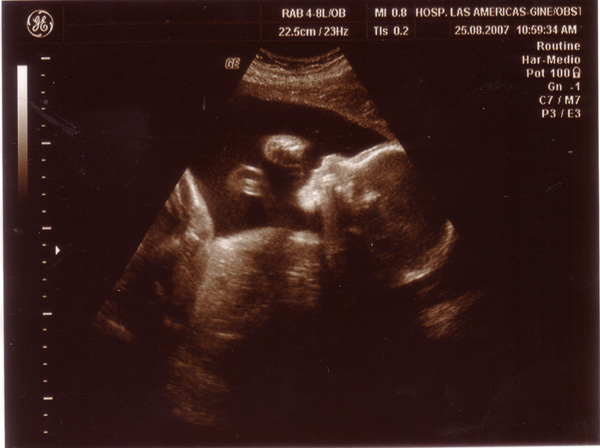

Lányok, mindenkinek köszönjük a dícséretet....egyébként úgy látjuk, hogy tiszta apuka

majd kiderül...még bízom benne, hogy a szeme az "enyém" lesz, mert ugyebár deréktól lefele is apuci, így már mondtam, hogy ha így lesz (s lehet, hogy egyébként is), akkor még egyet kell szülnöm ,hogy ő majd hátha rám hasonlít